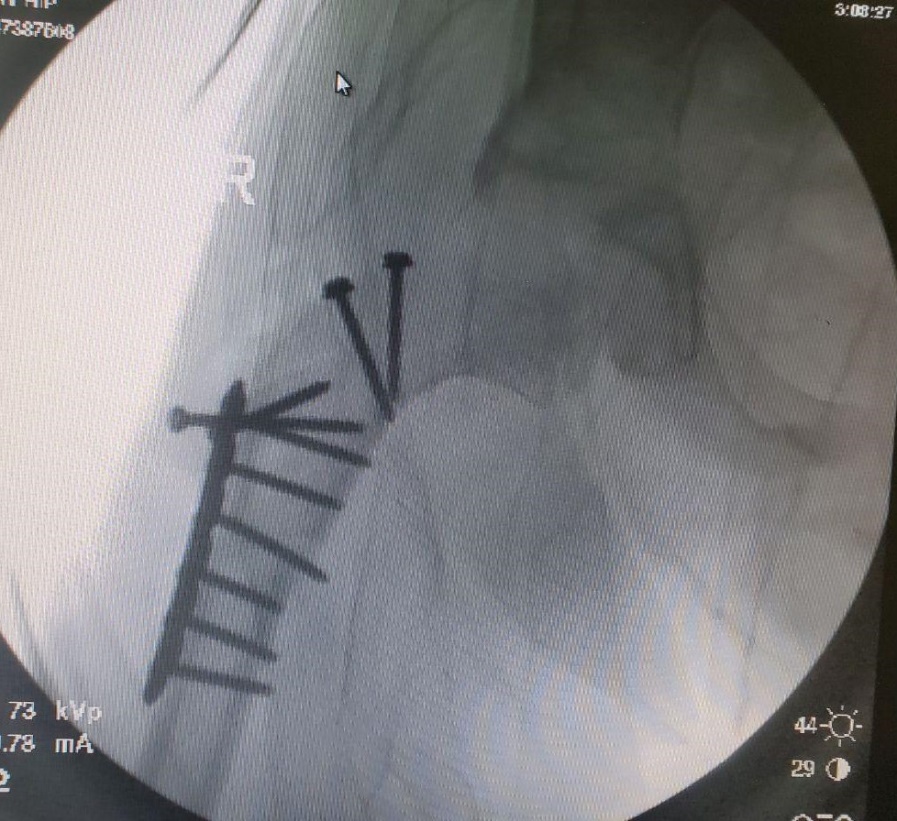

Head reduction — intraoperative view

Intraoperative view.

Head reduction — result

Result after head reduction.